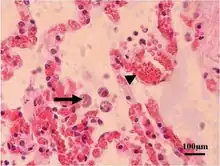

Acute toxoplasmosis is often asymptomatic in healthy adults.[13][14] However, symptoms may manifest and are often influenza-like: swollen lymph nodes, headaches, fever, and fatigue,[15] or muscle aches and pains that last for a month or more. It is rare for a human with a fully functioning immune system to develop severe symptoms following infection. People with weakened immune systems are likely to experience headache, confusion, poor coordination, seizures, lung problems that may resemble tuberculosis or Pneumocystis jiroveci pneumonia (a common opportunistic infection that occurs in people with AIDS), or blurred vision caused by severe inflammation of the retina (ocular toxoplasmosis).[15] Young children and immunocompromised people, such as those with HIV/AIDS, those taking certain types of chemotherapy, or those who have recently received an organ transplant, may develop severe toxoplasmosis. This can cause damage to the brain (encephalitis) or the eyes (necrotizing retinochoroiditis).[16] Infants infected via placental transmission may be born with either of these problems, or with nasal malformations, although these complications are rare in newborns. The toxoplasmic trophozoites causing acute toxoplasmosis are referred to as tachyzoites, and are typically found in bodily fluids.[17][18]

Skin

While rare, skin lesions may occur in the acquired form of the disease, including roseola and erythema multiforme-like eruptions, prurigo-like nodules, urticaria, and maculopapular lesions. Newborns may have punctate macules, ecchymoses, or "blueberry muffin" lesions. Diagnosis of cutaneous toxoplasmosis is based on the tachyzoite form of T. gondii being found in the epidermis.[31] It is found in all levels of the epidermis, is about 6 by 2 μm and bow-shaped, with the nucleus being one-third of its size. It can be identified by electron microscopy or by Giemsa staining tissue where the cytoplasm shows blue, the nucleus red.[32]

High magnification micrograph of toxoplasmosis -

Brain biopsy-High magnification micrograph of toxoplasmosis -

Immunohistochemistry displaying positive Toxoplasma gondii trophozoites in a brain biopsy of a HIV immunocompromised individual